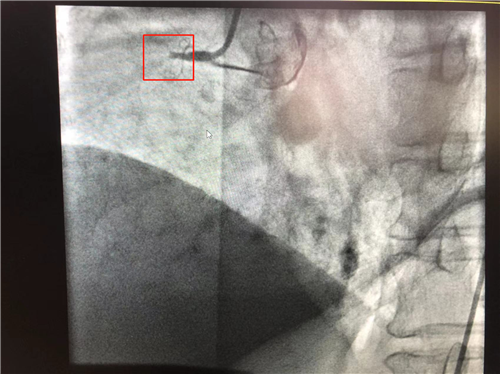

時間就是心肌,時間就是生命。導管室內(nèi),心血管內(nèi)科副主任徐先進、主任助理農(nóng)彥林已然待命,病人一到,團隊立即為其行深靜脈穿刺泵入血管活性藥物等,情況緩解后,行多體位冠狀動脈造影,確認RCA(右冠狀動脈)近端完全閉塞。經(jīng)家屬同意,在汪念東院長的指導下,徐先進、農(nóng)彥林、張星為患者行經(jīng)皮冠狀動脈球囊擴張成形術(shù)+經(jīng)外周靜脈穿刺中心靜脈置管術(shù)。術(shù)中,張奶奶再次出現(xiàn)室顫,心血管內(nèi)科團隊臨危不亂,立即予以300焦電除顫搶救,患者竇性心律恢復。隨后,球囊擴張為其置入心臟支架,復查造影顯示血管恢復暢通,無明顯夾層,殘余狹窄不到10%。術(shù)后,張奶奶血壓偏低,轉(zhuǎn)入ICU無創(chuàng)呼吸監(jiān)護,2天后轉(zhuǎn)回心血管內(nèi)科護理。

術(shù)前:右冠近端閉塞